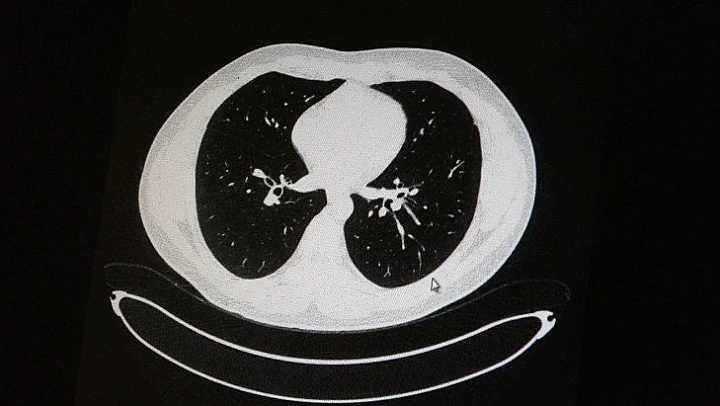

Elazığ'da öksürük, halsizlik, yorgunluk ve çabuk yorulma gibi şikayetlerle hastaneye başvuran ve korona virüs tespit edilen 2 genç hastadan aşısız olanının tomografi sonuçlarında virüsün akciğerlerde zatürreye sebebiyet verdiği görüldü. Aynı şekilde aşı olup korona virüs hastalığına yakalanan bir başka genç hastanın bilgisayarlı akciğer tomografisinde akciğerinde herhangi bir sorunun olmadığı belirlendi.

Medical Park Elazığ Hastanesi Göğüs Hastalıkları Uzmanı Dr. Cebrail Azar, geçtiğimiz yıla oranla yoğun bakımda yatan hastaların yaş ortalamasının 65'ten 35'lere kadar düştüğüne dikkat çekti. Genç olduğu halde aşı olmayanlarda hastalığın ağır seyrettiğini ifade eden Uzm. Dr. Azar, "Ben gencim, benim bağışıklık sistemim kuvvetli" diyen genç bir hastanın akciğerlerinde ciddi lekelenmelerin olduğunu ve korona virüs zatürresi olduğunu gördüklerini belitti. Uzm. Dr. Azar, aynı şekilde aşı olup korona virüs hastalığına yakalanan bir başka genç hastanın akciğer tomografisinde akciğerde herhangi bir sorunun olmadığını ve hastanın durumunun iyi olduğunu gözlemlediklerini kaydetti. Uzm. Dr. Azar, sürekli şahit oldukları "Keşke biz aşı olsaydık" sözünü bir daha duymamak için herkesi aşı olmaya davet etti.